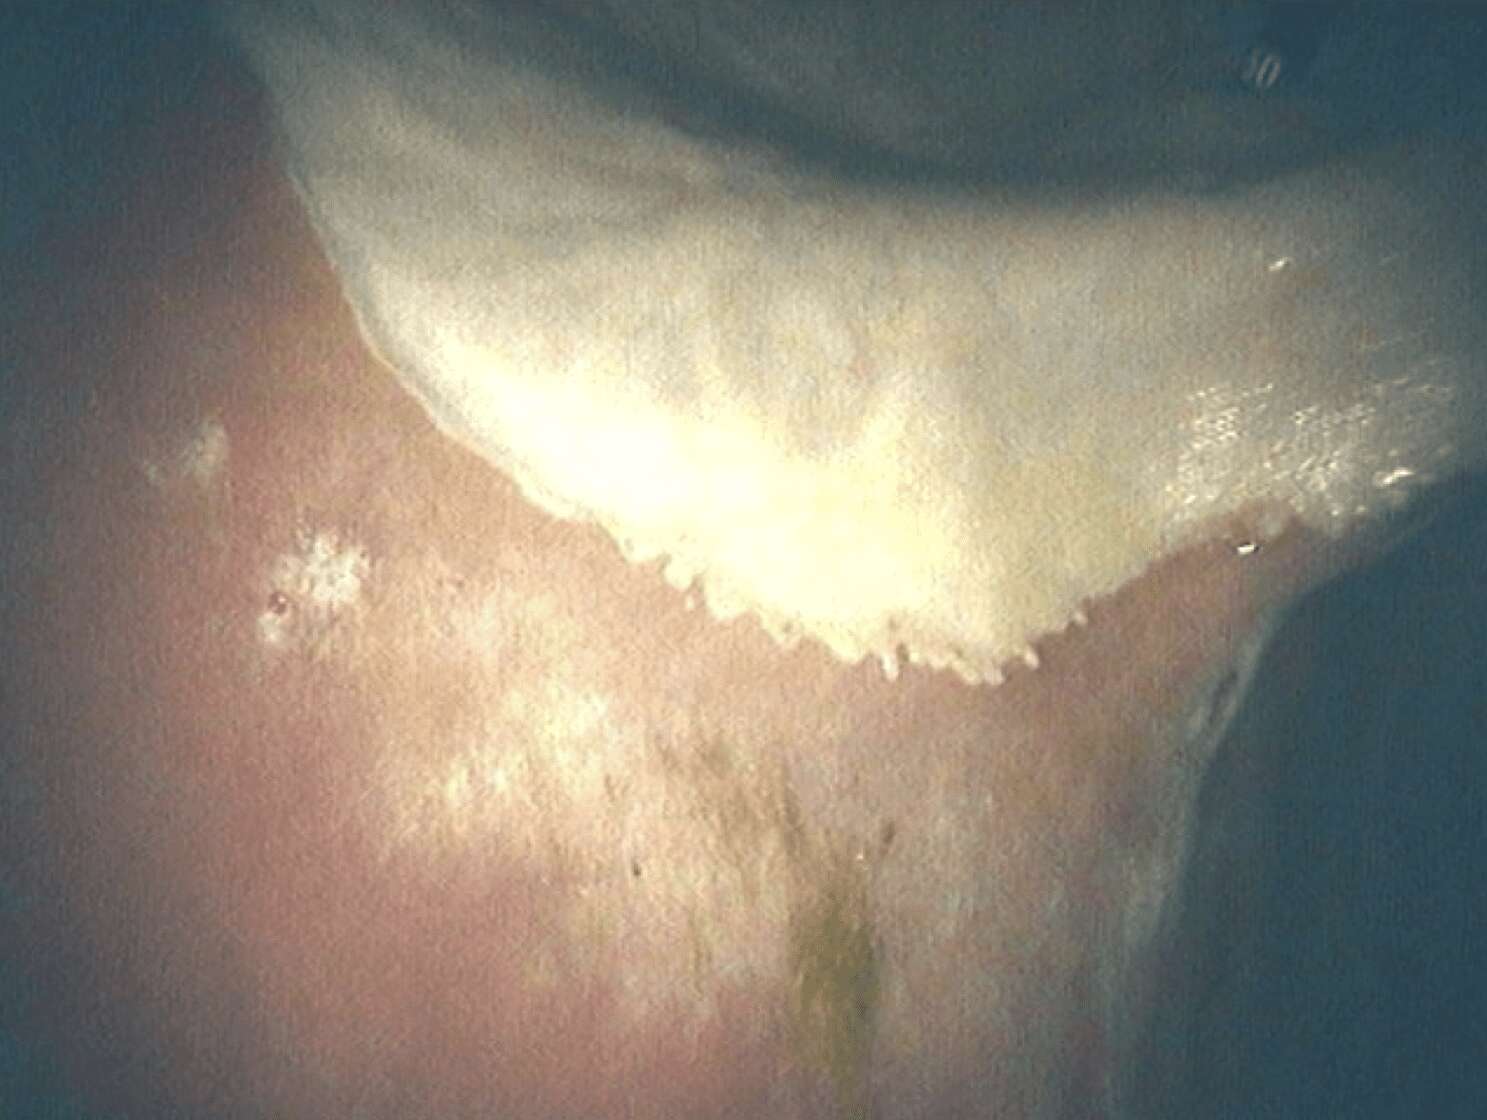

Greater, Lesser Curvature and Pylorus

You can also see the acid sat in the bottom of the stomach

Normal Pylorus / Exit